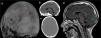

The case of a 7-year-old girl admitted for traumatic brain injury (TBI) with the diagnosis of a left parasagittal occipital sinus fracture that stenosed the posterior third of the superior sagittal sinus is presented. Upon arrival, she was asymptomatic, and conservative management was selected. Subsequently, the patient began to present with headache, nausea, vomiting and diplopia associated with bradycardia and apnoea pauses of central origin. She underwent surgery with a craniectomy with satisfactory clinical and radiological evolution and normalization of the intracranial pressure (ICP) registry.

Depressed fractures that occur on the superior sagittal sinus (SSS) cause stenosis or thrombosis of the sinus in 11.5% of cases. Despite this, the appearance of signs and symptoms derived from high intracranial pressure is an infrequent event. So far, only 17 cases of venous sinus injury causing intracranial hypertension have been documented. It is necessary to establish treatment immediately before clinical suspicion. Surgical treatment by craniectomy is a fast, effective and safe alternative according to the series. However, it is necessary to anticipate the possibility of haemorrhage in the operating room.